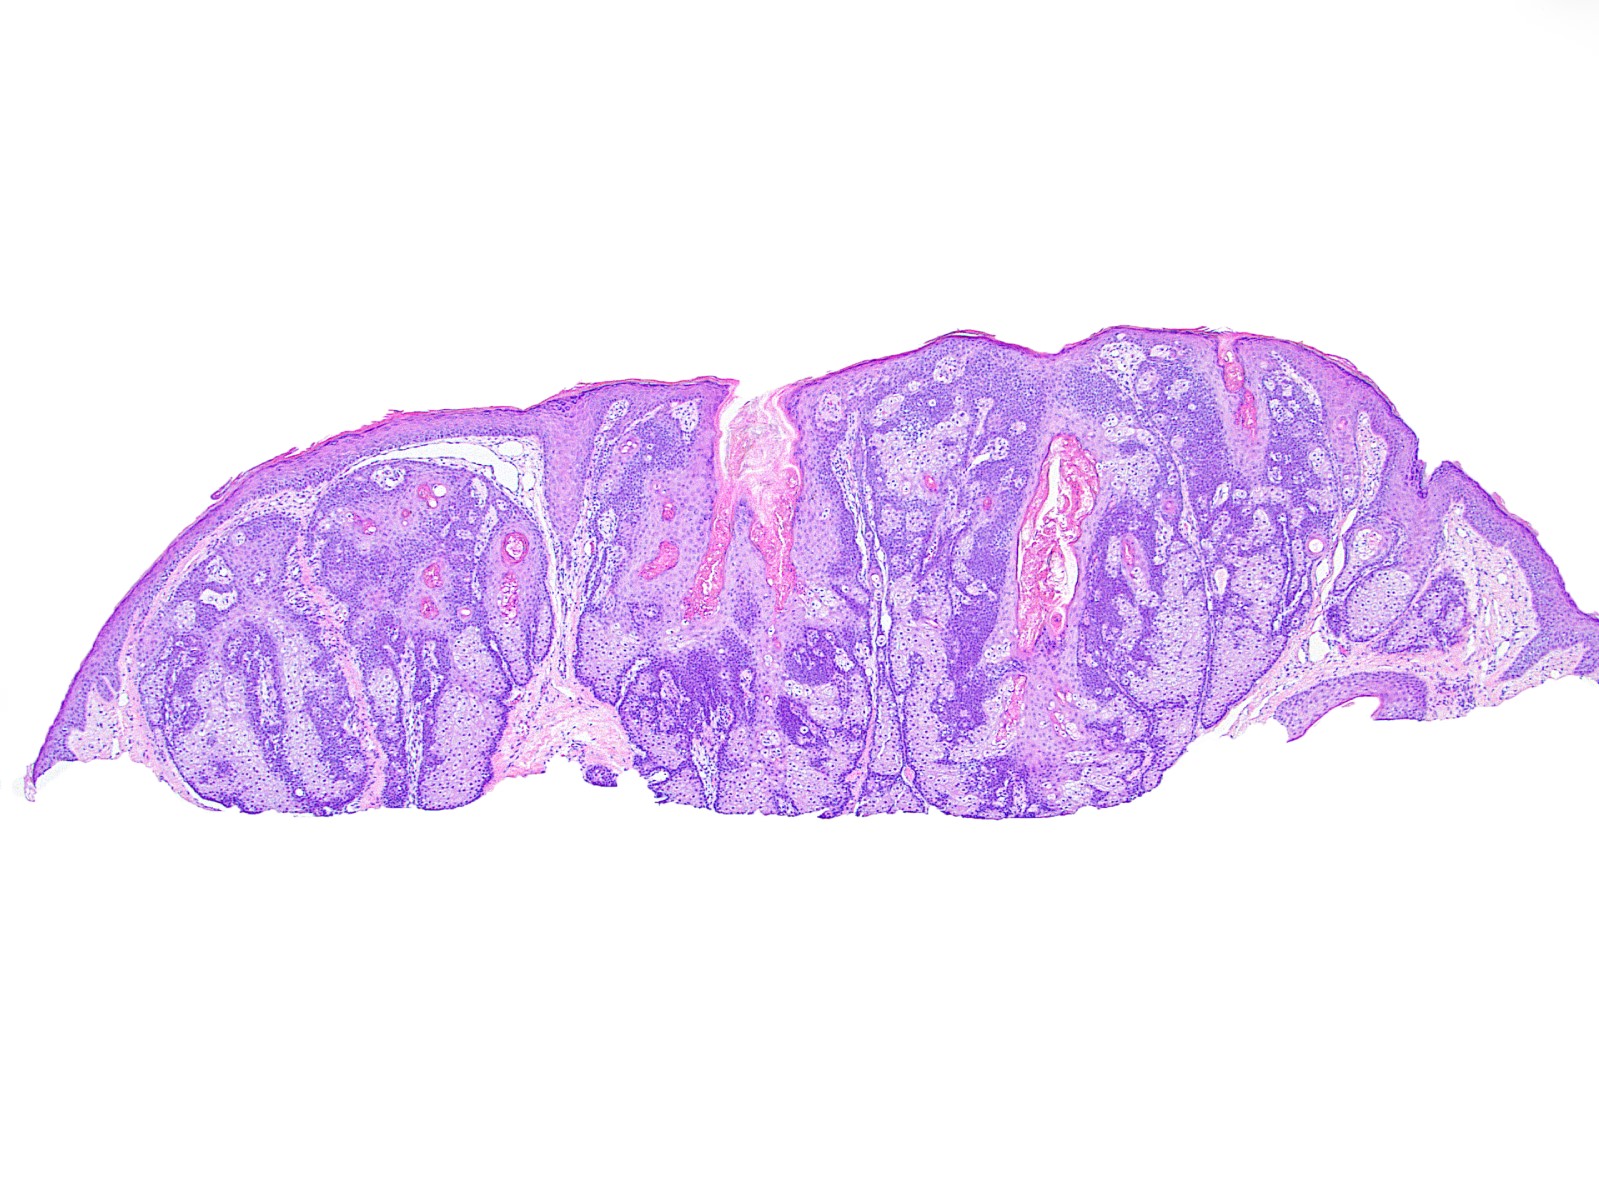

Microscopic (histologic) images

- Well circumscribed, nodular growth of lobules consist of admixture of basaloid cells and mature sebocytes

- Some lobules may communicate directly with the surface epithelium

- Basaloid cells are usually located at the periphery of lobules and sebaceous cells with intracytoplasmic lipid vacuoles, which are usually located at the center of lobules

- Basaloid cells are composed of expanded germinative layer, with more than the normal 2 cell layers seen in mature sebaceous glands or sebaceous hyperplasia but still less than 50% of the tumor volume (> 50% is seen in sebaceoma / sebaceous epithelioma)

- Increased mitotic activity is sometimes seen in the basaloid cell component (Surg Pathol Clin 2017;10:367)